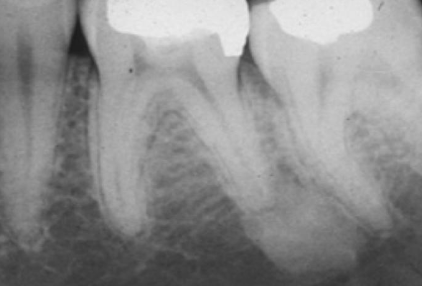

how would you describe this radiographic lesion?

an apical well-defined radiopaque lesion